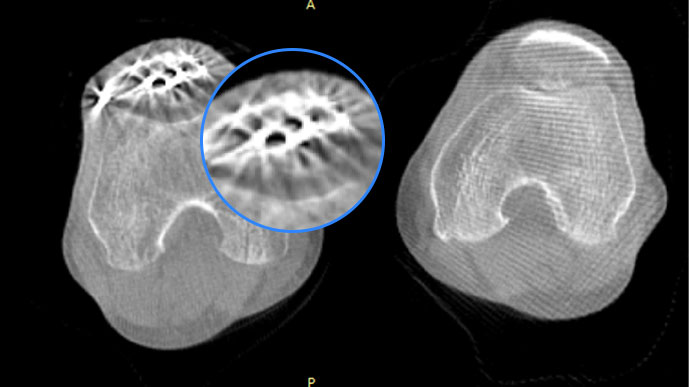

膝關(guān)節(jié)

關(guān)閉金屬偽影校正

開(kāi)啟金屬偽影校正